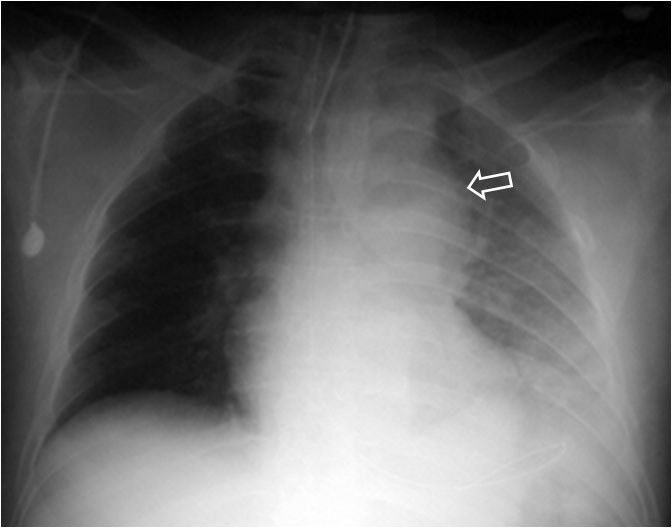

La aparición de una densidad en el ápex pulmonar izquierdo, de borde inferior cóncavo y bien delimitado (casquete apical) en un paciente con traumatismo torácico, debe hacernos sospechar la existencia de una rotura aórtica.

Deben excluirse otras causas de casquete apical, especialmente las lesiones residuales tuberculosas, que suelen acompañarse de otros hallazgos como tractos fibrosos pleuro-parenquimatosos, pérdida de volumen en el lóbulo superior, granulomas, etc.

Mostramos un caso de rotura aórtica por accidente de moto. En este paciente también aparece el signo de la alteración del contorno aórtico.